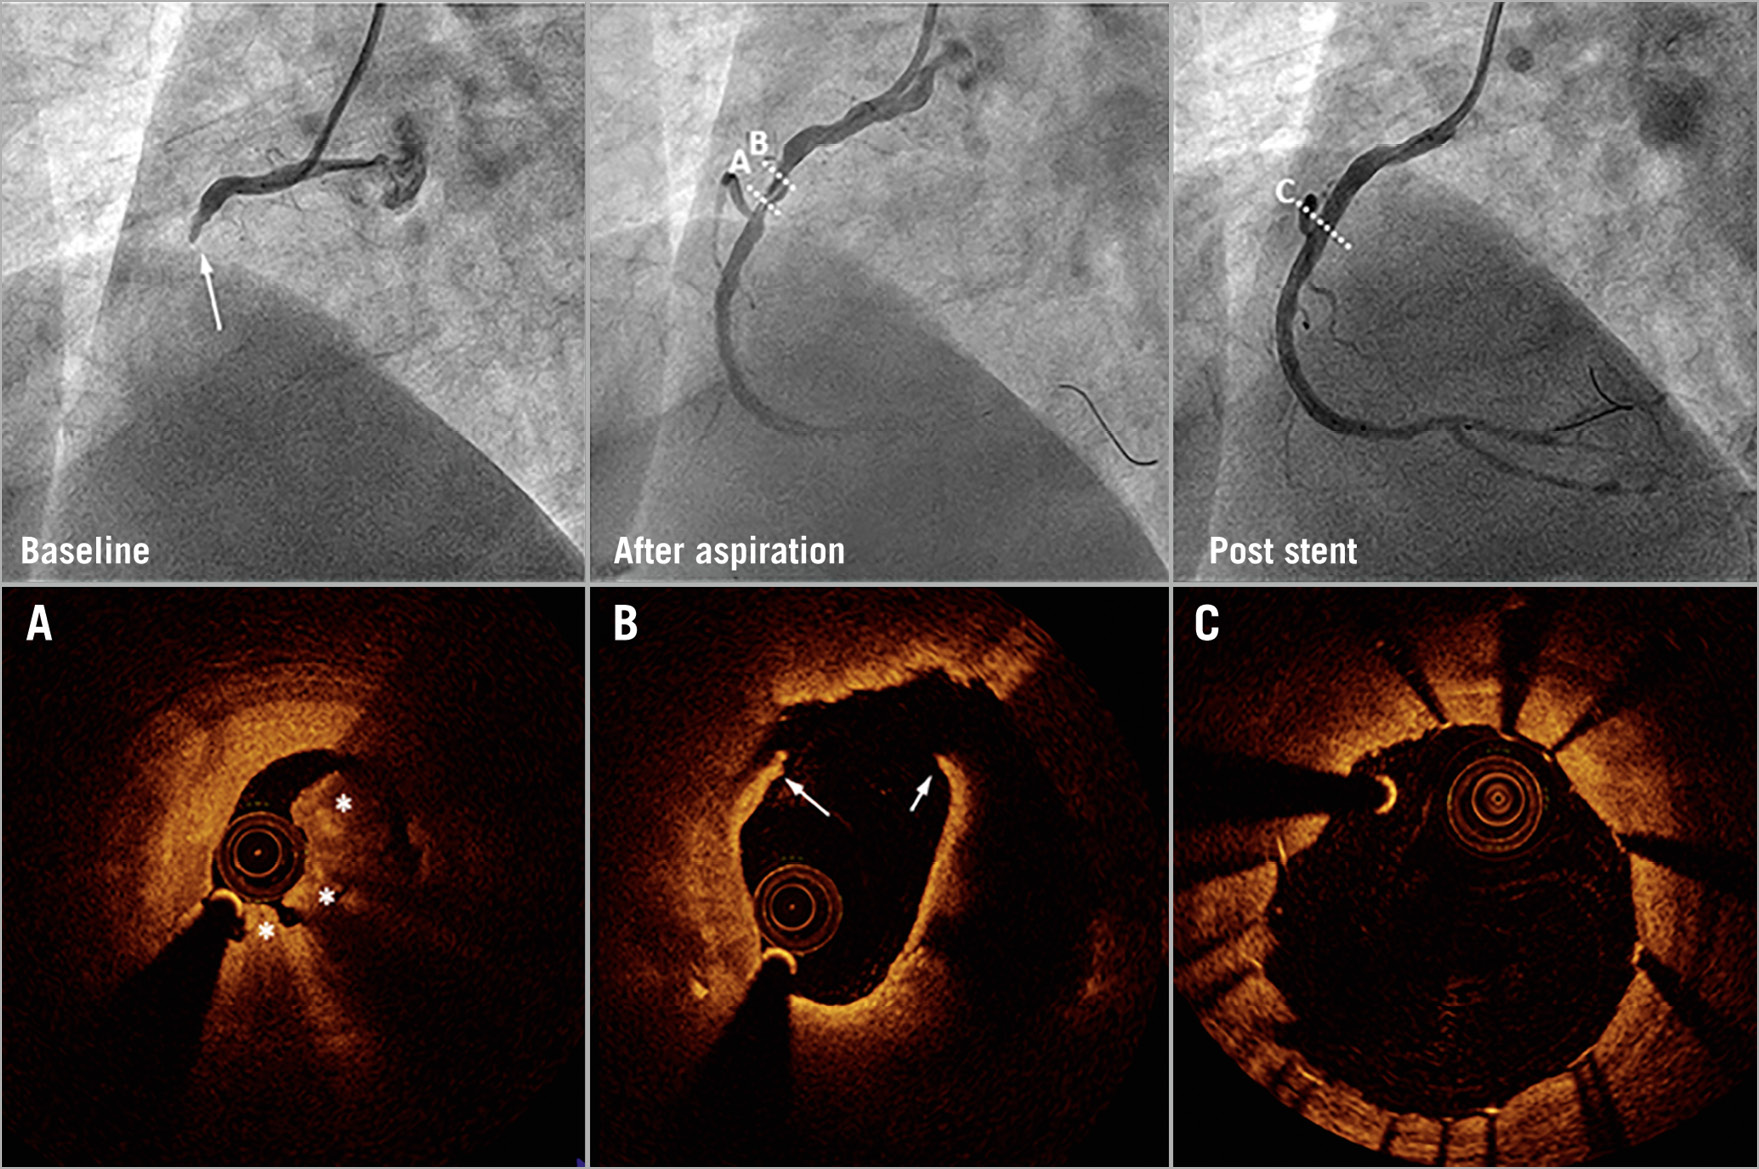

Figure 3. Coronary angiography and optical coherence tomography in a control patient. Baseline angiography (upper left) shows a patient with complete occlusion and TIMI 0 flow. After thrombus aspiration, the coronary arterial flow was restored to TIMI 3 flow. Optical coherence tomography (OCT) shows plaque rupture (white arrows) and red thrombus (white stars) (A & B). Angiography and OCT show imaging of the region after stent implantation (C).